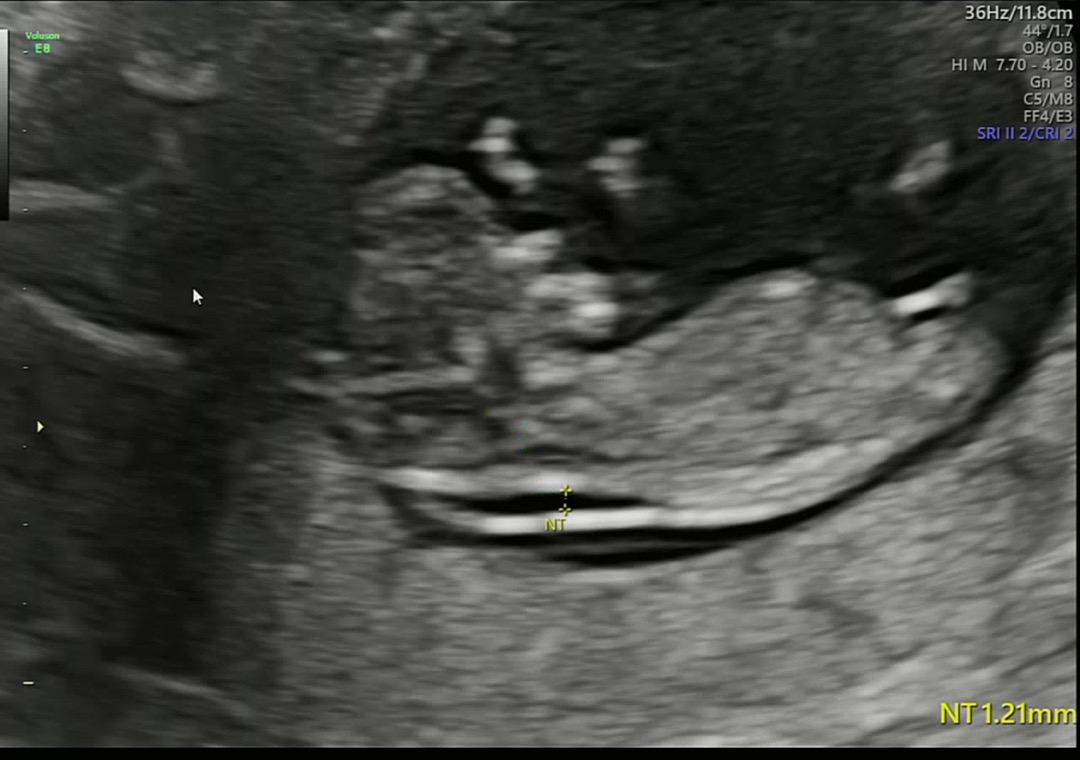

각도법 봐주세요!

궁금해요 🫣